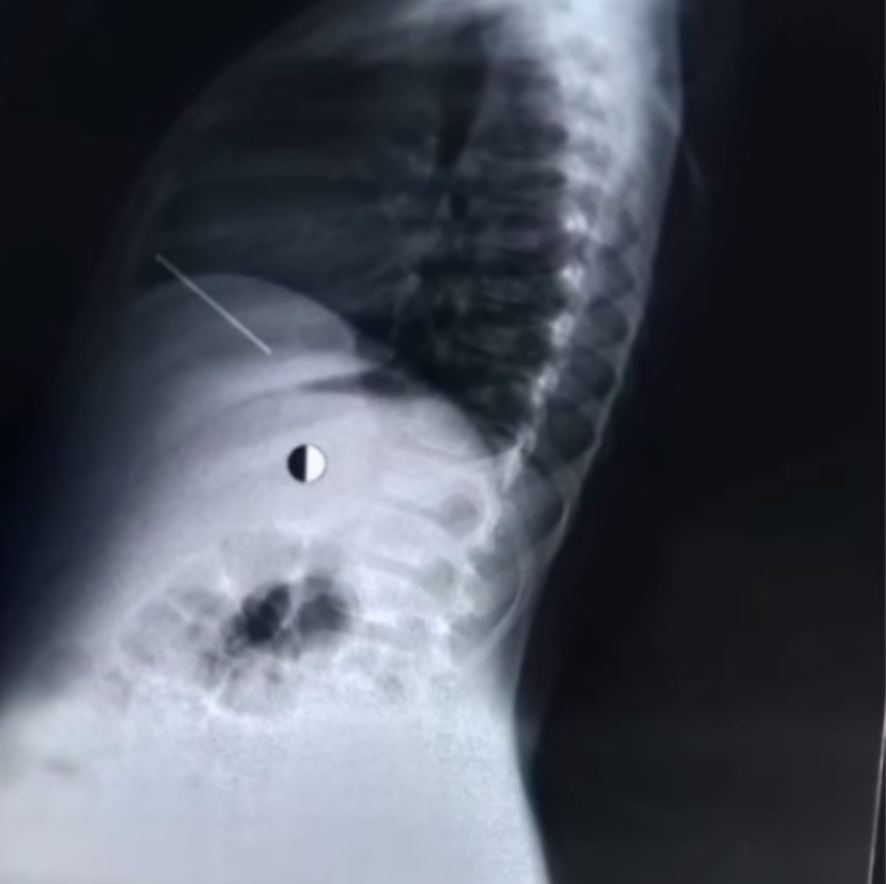

نجح فريق طبي من مستشفى قصر العيني التابع لمستشفيات جامعة القاهرة في استخراج مسمار بطول 5 سم من طفل يبلغ من العمر 8 سنوات، وذلك بعد تعرض الطفل لـ حادث طلق بمسدس مسمار، أصاب الطفل بمحيط القلب.

وتابع: بعد إدخال المريض إلى المستشفى وتجهيزه جرى نقله إلى وحدة عمليات القلب والصدر، مؤكدا أنه تم اتكشاف المسمار من خلال فريق الصدر، وتم العثور على المسمار يخترق البريكارديوم بالقرب من الأذين الأيمن ونقير الرئة اليمنى، وجرت إزالته بدون مضاعفات على يد جراح القلب الكبير الدكتور حسام فتحي، ويعاونه المدرس المساعد أحمد علام وطبيب القلب المقيم أحمد محمد كامل.